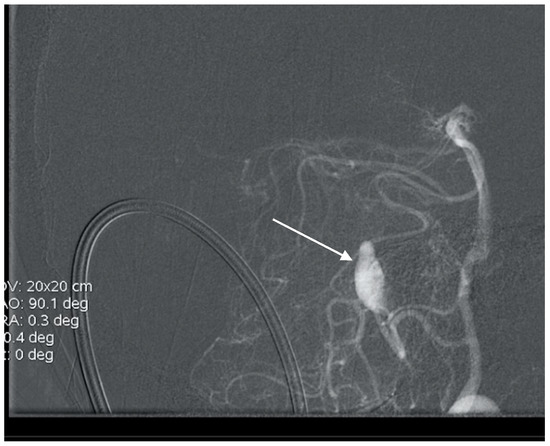

A 57-year-old female hypertonic patient was admitted to the neurology unit of a regional hospital in a mild Hunt and Hess grade for sudden-onset headache and vomiting. Computed tomography (CT) confirmed Fischer grade 2 subarachnoid hemorrhage (SAH). Following atypical angiography findings, an aneurysm on the bifurcation of the basilar artery (BA) was suspected (Figure 1), and the patient was urgently referred for endovascular treatment. Following catheter placement and 3 Dimensional—Digital Subtraction Angiography imaging, an aneurysm on the peripheral branch of the SCA was found, which was inaccessible for endovascular treatment due to the luminal diameter of the vessel. An additional MRI confirmed the suspected location and gigantic size of the partially thrombosed lesion, and the patient was prepared for surgery. With a midline supracerebellar approach, trapping of the parent artery and extirpation of a large (15 × 18 mm) thrombosed sac with preservation of the precentral vein were performed. Histological findings were without surprise; no mycotic agents or bacterial inflammation in the aneurysmal wall were revealed. Her postoperative course was uneventful, and follow-ups are undertaken every year.

Figure 1. Angiogram misdiagnosed as aneurysm of bifurcation of the basilar artery (BA) in case report 1.